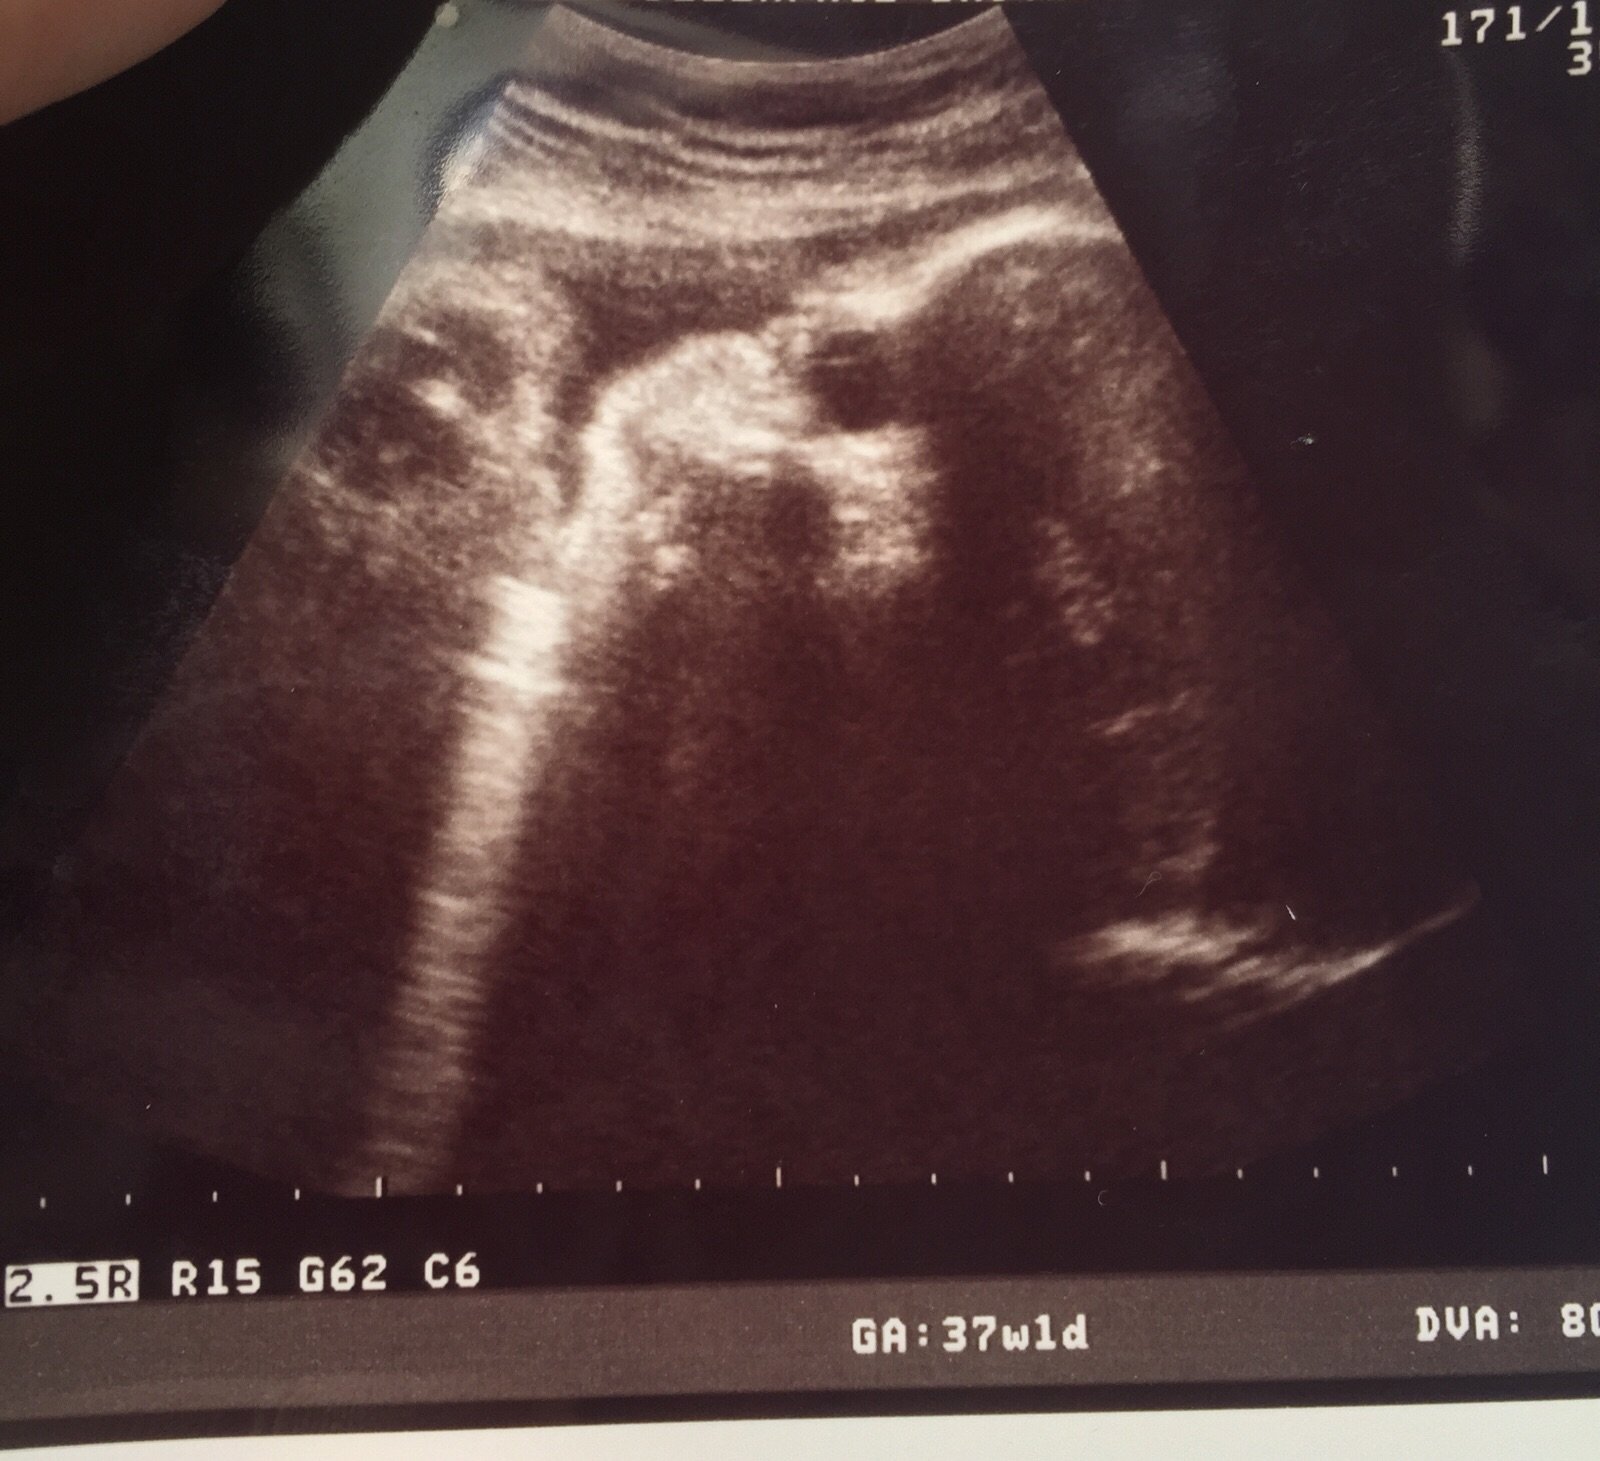

• 37 weeks today. Had my appt, urine good, BP good. Did a second GBS swab because the first result was missing... Only to locate the results minutes after the second swab. Had an intense cervical check, still 1cm, now 75% effaced and I kind of wonder if there may have been some stripping going on. Lost my plug last week and there's been some bleeding and cramping so far tonight.

• 37 weeks & couple days. 1 cm. Everything is progressing excellent!

• Today at 37.2 I was still less than 1cm dilated, but 70% effaced which doc said was good. Head still high but lower than last week.

Second doc now estimating baby at 7 lbs or so... So we may be looking at an 8 pounder!

Lastly, I knew she moved a lot last week. Yep, she's still head down but turned her body and is either on her side or sunny-side up. Boo! She was in the correct position for the last few months, and now she decides it's not comfy??